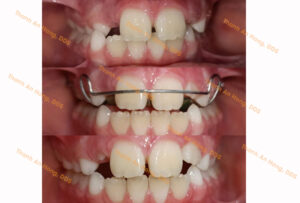

HÌNH ẢNH THỰC TẾ

Chỉnh lệch mặt trong độ tuổi tăng trưởng bằng khí cụ